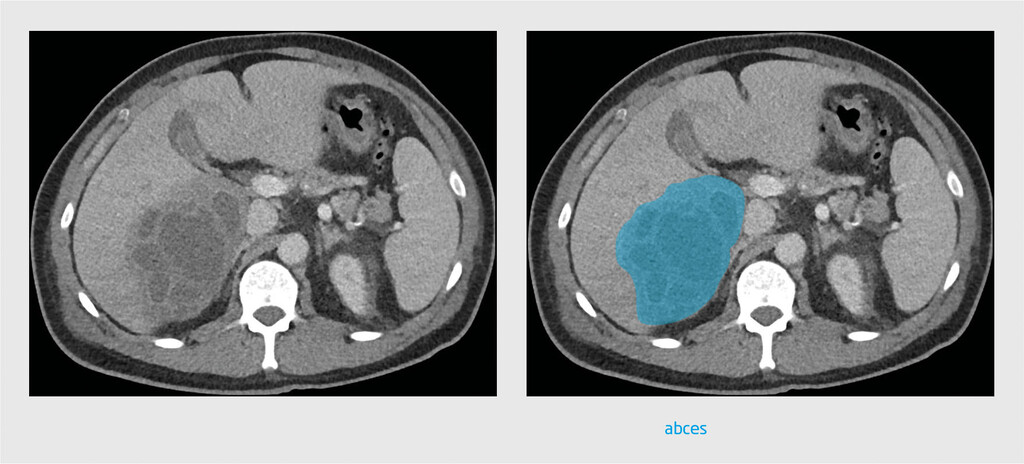

Patiënt A, een 46-jarige man met blanco voorgeschiedenis, meldde zich op de Spoedeisende Hulp met koorts, koude rillingen en dyspneu sinds 3 dagen. Bloedonderzoek toonde verhoogde leverenzymwaarden en sterk verhoogde infectieparameters. Er werden bloedkweken afgenomen. Op de X-thorax werd een mogelijk infiltraat in de rechter hilus gezien. Patiënt kreeg amoxicilline voorgeschreven bij de werkdiagnose ‘pneumonie’ en ging weer naar huis. De bloedkweek toonde 3 dagen later Fusobacterium necrophorum aan. Daarop werd patiënt opgenomen. Er werd een CT-hals/thorax/abdomen verricht, dat een leverabces met een diameter van ongeveer 5,7 cm toonde (figuur 1). De CT toonde geen tromboflebitis in de V. jugularis interna. Bij navraag bleek dat de patiënt 3 maanden eerder een wortelkanaalbehandeling had ondergaan, wat mogelijk de bron was voor het leverabces. De diagnose werd bijgesteld naar pyogeen leverabces, mogelijk syndroom van Lemierre. De patiënt werd behandeld met intraveneus cefuroxim en metronidazol. Het leverabces werd gedraineerd middels echogeleide punctie en uit het drainagevocht werd eveneens Fusobacterium necrophorum gekweekt.

Vanwege de verdenking op een maligniteit werd CT verricht. De CT-scan toonde een leverabces in leversegment V (figuur 2). Daarop vond drainage van het abces door echogeleide punctie plaats. Kweek van drainagevocht toonde een Fusobacterium nucleatum aan . De behandeling bestond uit intraveneuze toediening van ceftazidim en metronidazol. Bij navraag bleek de patiënt 4 maanden eerder een kiesextractie te hebben ondergaan, wat de bron van de infectie geweest zou kunnen zijn.